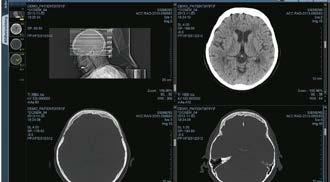

Der neue Computertomograph Aquilion Exceed LB von Canon Medical ist ein Multitalent mit wahrer Größe. Das System wurde für insbesondere für den Einsatz in der Traumatologie sowie für die Bestrahlungsplanung entwickelt. Für beide Anwendungsgebiete ist die Gantryöffnung von 90 Zentimetern ein großer Vorteil. Zum einen schafft der große Durchmesser ausreichend Platz für adipöse Patienten, zum anderen profitiert die Strahlentherapieplanung von einem besonders großen Field-ofView, denn damit sind selbst komplexe Lagerungssituationen einfach zu realisieren. Außerdem ist es mit dem System leicht möglich, Patienten in Feet-first-Position zu scannen. So müssen sie entweder gar nicht oder nur kurz mit Kopf in die Gantry gefahren werden.

Zudem ermöglicht die neue Geometrie des Aquilion Exceed LB Untersuchungen bis zu einem Patientengewicht von 315 Kilogramm bei einer maximalen Scanlänge von zwei Metern.

Perfekt für die Trauma-CT Weitere Highlights des Aquilion Exceed LB sind der ebenfalls neue 80-Zeilen-Big-bore-Detektor mit einer Abdeckung von vier Zentimetern und die Rotationszeit von nur 400 Millisekunden. 80 Zeilen und vier Zentimeter Abdeckungen sorgen für eine Schichtbreite von lediglich 0,5 Millimetern. Und in Kombination mit der Rotationszeit von 400 Millisekunden ist das System in der Lage, je Sekunde bis zu 70 ultrahochauflösende Dünnschichtscans zu rekonstruieren. Für eine komplexe Diagnostik der Anatomie von Herz oder Brustkorb sind das ideale Voraussetzungen, denn so können mit hoher Geschwindigkeit hochwertige Bilder erstellt werden. Die technischen Rahmenbedingungen sorgen dafür, dass der Scan robuster gegen unerwünschte Patientenbewegungen ist und die Notwendigkeit einer Zweituntersuchung reduziert wird. Für den Therapieerfolg gilt eine präzise und reproduzierbare Patientenpositionierung als wichtiger Baustein. Speziell in der CT-basierten Bestrahlungsplanung ist ein möglichst großes Field of View (FOV) vorteilhaft. Die Gantryöffnung des Aquilion Exceed LB,

Der neue Aquilion Exceed Large Bore CT von Canon Medical Systems wurde gleichermaßen für die Notaufnahme wie für die moderne Strahlentherapieplanung entwickelt.